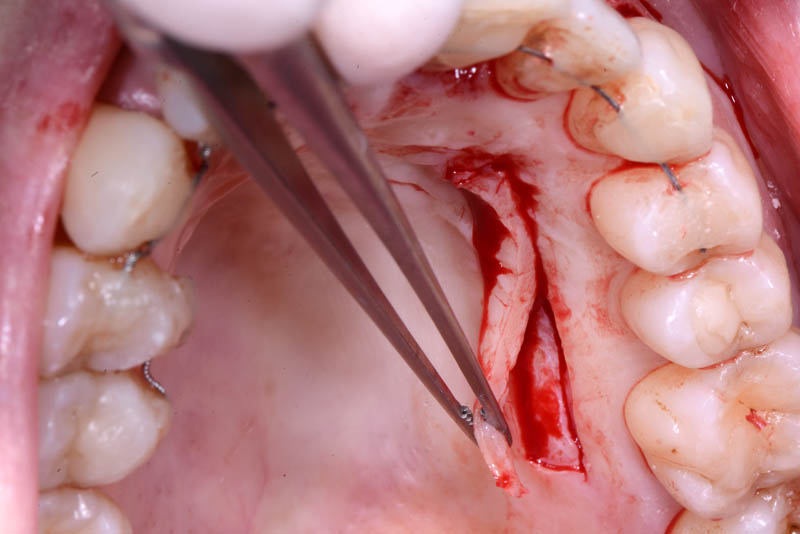

At the end of the orthodontic treatment, a coronally advanced flap was performed according to the De Sanctis and Zucchelli technique, involving papilla preservation and connective tissue grafting, to restore the gingival contour and the papilla between teeth 21 and 22.

connective graft

Emdogain Straumann